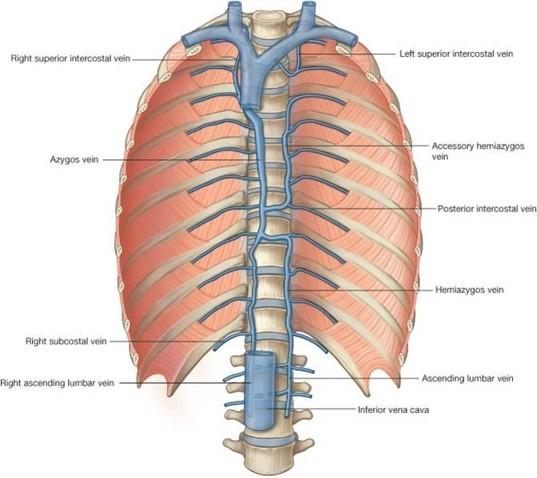

point out the azygos vein, the accesorry hemi-azygos vein and the hemi-azygos vein?

the azygos vein is on the right side under the big "faucet" going up

you can see a divit on the left side where the accessory hemi and hemi azygos travel behind and into the right side

the accessory hemi-azygos vein is the vein on the left side connecting the intercostal spaces from above the divit (on top)

the hemi-azygos vein is below the divit (on bottom)

overall, the "azygos system":

- drains what 2 things?

- consists of what 3 veins?

- “azygos system” also receives blood from where?

- this system acts as “collateral pathway” to “bypass” what?

the back & thoracoabdominal walls

azygos, hemi-azygos and accessory hemi-azygos veins

trunk and lower extremities

the IVC (inferior vena cava)

accessory hemi-azygos vein:

- receives blood from ______________ intercostal spaces

- Accessory hemi-azygos vein crosses midline and drains into where?

- NOTE: left side 1st – 4th intercostal spaces drain directly into where?

left side 5th - 8th

the azgos vein

left brachiocephalic vein

look at picture

hemi-azygos vein:

- receives blood from where?

- also receives blood from what other 2 left places?

- Hemi-azygos vein crosses midline and drains into __________?

left side 9th - 11th intercostal spaces

abdominal/pelvic trunk and lower extremity

azgos vein

look at picture

how is the lumbar veins a plan B?

they are a plan B in case there is some sort of obstruction in the inferior vena cava

(look at ascending lumbar vein in picture)

what do the right and left common illiac veins take care of?

the legs

azygos vein:

Receives blood from what 3 places?

Azygos veins continues on to drain into the ___________?

right side intercostals

hemiazygos & accessory hemiazygos veins

also receives blood from right abdominal/pelvic trunk and lower extremity

SVC (superior vena cava)

notice how it gets blood from the hemi azygos and accessory azygos and how it travels up into the SVC